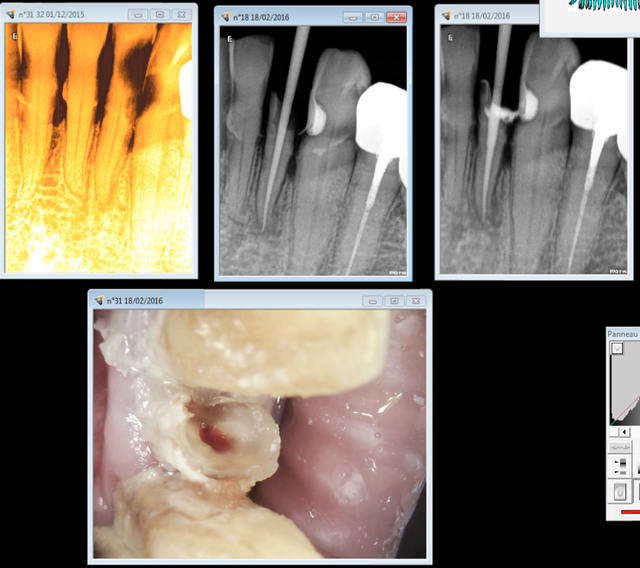

Là non plus je ne savais pas que ca allait se terminer en endo. Curetage - effraction pulpaire.- endo Donc hbqk040.

Capture d e cran 2016 02 22 14.43 - Eugenol